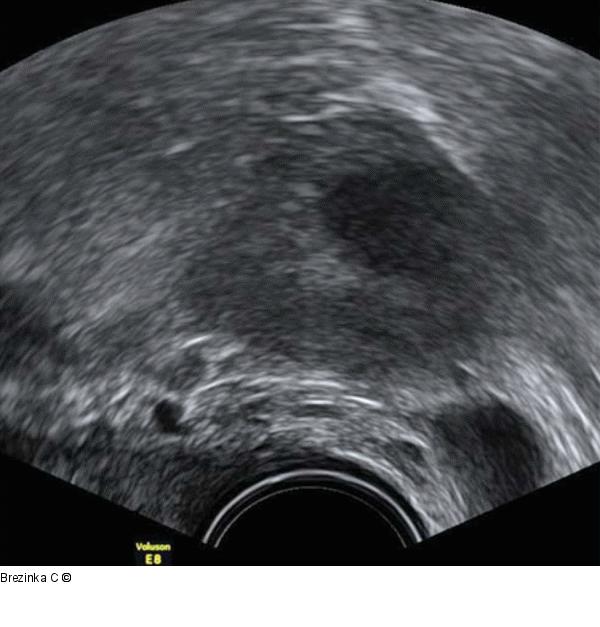

Abbildung 4: Gyn-Ultraschall Eine echoarme Auflockerung bleibt als Rest eines Corpus luteum am 2. Zyklustag des nächsten Zyklus. Im Farbdoppler zeigt sich keine Vaskularisation. |

Eine echoarme Auflockerung bleibt als Rest eines Corpus luteum am 2. Zyklustag des nächsten Zyklus. Im Farbdoppler zeigt sich keine Vaskularisation. |